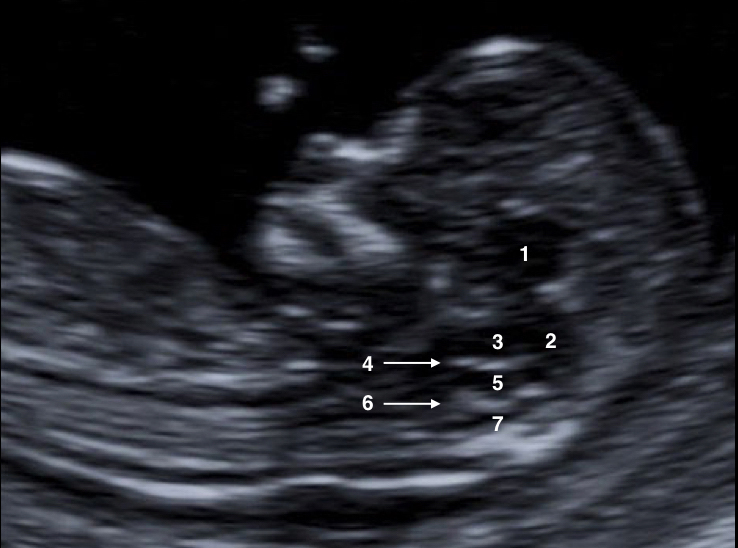

Evaluación del sistema nervioso central en primer trimestre

Durante el primer trimestre tardío es posible estudiar la anatomía del cerebro fetal. La vía transvaginal optimiza la visualización de las estructuras endocraneales en esta etapa de la gestación.  A través de un corte axial de la calota fetal, se puede demostrar la morfología normal de ésta, medir el diámetro biparietal (DBP) y examinar el contenido intracraneal, cuyas estructuras más prominentes son los plexos coroideos separados por la hoz del cerebro. A nivel de los ventrículos laterales, los plexos coroideos adoptan normalmente una morfología que remeda a la de una mariposa (signo de la mariposa) (Figura 5). En una sección axial transtalámica, entre ambos plexos coroideos se puede apreciar el tercer ventrículo (3V) como una pequeña estructura anecoica localizada en el centro del encéfalo. También se pueden observar los tálamos, el cerebro medio y el acueducto de Silvio ubicado en una posición más posterior. El acueducto de Silvio (AS) es facilmente idenficable en el primer trimestre y aparece como una estructura rectangular a nivel del mesencéfalo (Figura 6). Con respecto al cerebelo, entre la semana 11 y 12, es unaestructura muy pequeña y se lo localiza por encima del cuarto ventrículo (4V). Este se encuentra delimitado por una membrana delgada y se individualiza en un corte axial fronto-occipital. Progresivamente ocurre la unión de los hemisferios cerebelosos y el desarrollo del vermis. En un corte axial oblicuo, a nivel de la fosa posterior, se puede identificar el tronco cerebral (TC), cuarto ventrículo (4V) y cisterna magna (CM) (Figura 7).                                                                                                                           En el corte sagital medio de la cabeza en un feto de 12 semanas, utilizado habitualmente para la medición de la translucencia nucal, se logran individualizar estructuras intracraneales de la línea media como el TC, el 4V y la CM. El 4V representa a la translucencia intracranial (TIC) paralela a la translucencia nucal y se encuentra delimitada por dos bordes ecogénicos, la parte dorsal del tronco cerebral, hacia anterior; y los plexos coroideos, hacia posterior. Embriológica y anatómicamente la llamada TIC corresponde al fluido cerebro-espinal en el área membranosa anterior del 4V en desarrollo.  Por debajo del 4V, entre éste y el occipital, se observa otra área anecoica delgada que corresponde a la CM y por encima del 4V otra región ecolúcida correpondiente al tronco cerebral que se sitúa por debajo del diencéfalo.

Los reparos antes descriptos generan por debajo del diencéfalo, tres áreas anecoicas que corresponden en sentido descendente al tronco encefálico, el 4V y la CM respectivamente (Figura 8). Estas cavidades se encuentran a la vez enmarcadas por cuatro líneas sucesivas, casi paralelas que en sentido descendente, corresponden al borde superior e inferior del tronco cerebral; la tercera, a los plexos coroideos del 4V; y la cuarta al hueso occipital (Figura 9). Es importante reconocer también la relación del tamaño entre la primera de estas áreas, que corresponde al troco cerebral, y la sumatoria de las otras dos, la distancia entre el tronco cerebral y el occipital (DTCO). Como puede verse en la figura 10, en condiciones normales la DTCO es mayor al diámetro del TC y genera una relación TC/DTCO menor de 1.